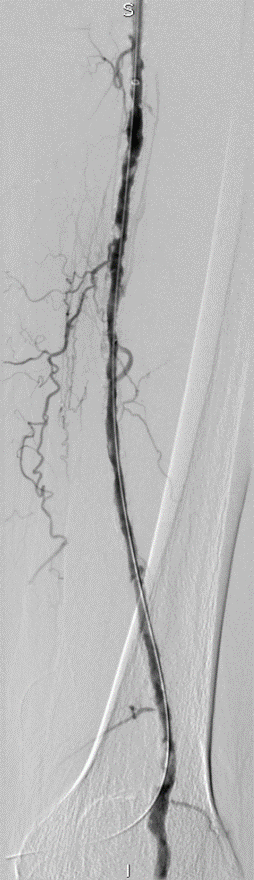

★ Case 5

Female,82 y

Severe claudication over 1 year in both extremities esp. in the left

DM over 10 years

CTA:SFA-PA long CTO

左右滑动查看